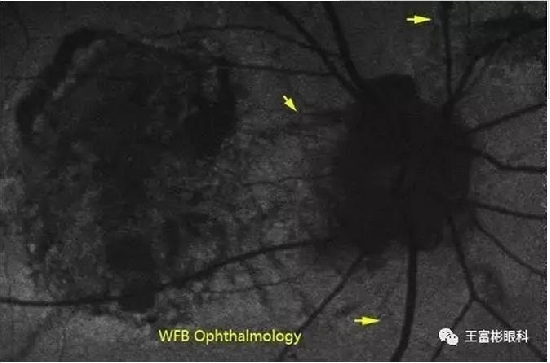

“血管样条纹”的FA/ICG影像

FA和ICG都可以显示血管样条纹的改变,但是相比较来说,ICG可能显示的更为清楚,并且常常能发现FA未能查及的病变。

关于FA,不一定像有些说的一定呈强荧光,也可以是弱荧光,这可能与“条纹”的色素状况和纤维组织增殖的程度有关。